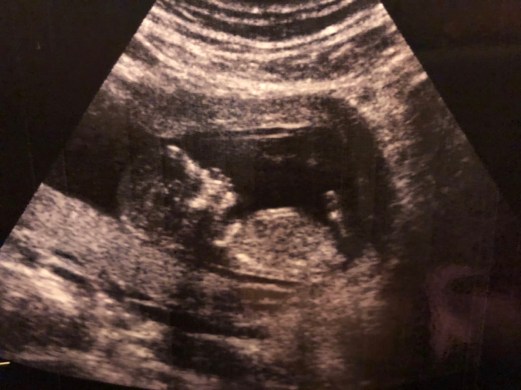

I was excited until week 6 when I started throwing up and I couldn’t eat or drink or smell. Jesus kept telling me it was all in my head. All I wanted was to throw up in his face so then it would be “all in his head.” The nausea and vomiting lasted until week 17. I am hoping it doesn’t return. On Dec 8th we saw our baby’s strong heart beat in an ultrasound. On Jan 18th we found out we were having a girl through our 2nd ultrasound. On March 6th we had our 20 week ultrasound and my Dr said the baby is perfect, healthy, no abnormalities and everything is going the way it should. Thank you God!